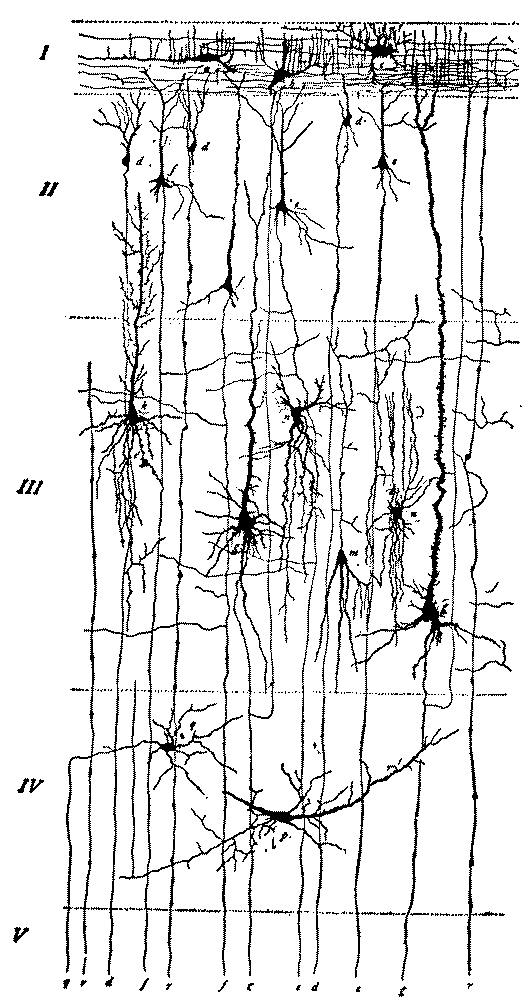

| 5. | First, second and third layer of the anterior central convolution of the brain of a child one month old | 112 |

| 7. | Diagram of cells of cerebral cortex | 113 |

| 8. | Scheme of lower motor neuron | 114 |

| 9. | Scheme of the visual conduction paths | 115 |

| 10. | Schematic frontal section through the occipital lobe illustrating manifold connections in a single lobe | 116 |

| 13. | Deep layer of giant pyramidal cells of the posterior central or ascending parietal convolution of a child thirty days old | 119 |